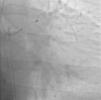

Case reportA 60-year-old-man with hypertension and type 2 diabetes as coronary risk factors was admitted to our hospital due to unstable angina. He had suffered a non-Q-wave myocardial infarction in 2006, when percutaneous coronary intervention (PCI) was successfully performed on the mid segment of the left anterior descending (LAD) and second obtuse marginal arteries. A coronary angiogram after the recent event showed a significant calcified lesion in the LM and ostial LAD without evidence of restenosis in the previous stents (Figures 1 and 2). The patient had severe left ventricular dysfunction, with 30% of ejection fraction. We planned PCI on the LM and LAD with intra-aortic balloon pump support.

The procedure was performed by radial approach using a 7F guiding catheter. Plaque preparation was performed with rotational atherectomy using a 1.5 mm burr (Figure 3) and further predilation with a cutting balloon (3-3.5 mm). After balloon dilatation, rupture of severely calcified plaque was detected by IVUS (Eagle Eye; Volcano Corporation, Rancho Cordova, CA, USA), so we proceeded to implant a 3.5 mm×20 mm CRE 8 DES in the LM and LAD (Figures 4 and 5). At this point the wire was accidentally pulled back and was reintroduced into the LM and LAD. Post-dilatation was performed with a 4 mm non-compliant balloon. IVUS examination with manual pull-back at this stage revealed that the proximal part of the stent in the LM had been crushed as a result of lateral reintroduction of the wire through a proximal stent strut. The patient remained stable with normal flow in the LM and LAD. Guided by IVUS, a second wire (Sion, Asahi Intecc, Japan), with a 30° bend in its 1 mm distal tip, was introduced within the crushed stent segment (Figure 6). Once the guidewire was positioned inside the stent, progressive dilations with small (1.5 mm) to large (4 mm) balloons were performed until the stent regained its cylindrical shape (Figure 7). IVUS exploration detected an image suggesting dissection in the proximal end of the stent (Figure 8), and so a second DES (4 mm×8 mm Onyx) was implanted in the ostial-proximal segment of the LM, overlapping the previous stent (Figure 9), with an adequate angiographic final result (Figures 10 and 11). IVUS revealed correct stent expansion and apposition in the LM (Figure 12).